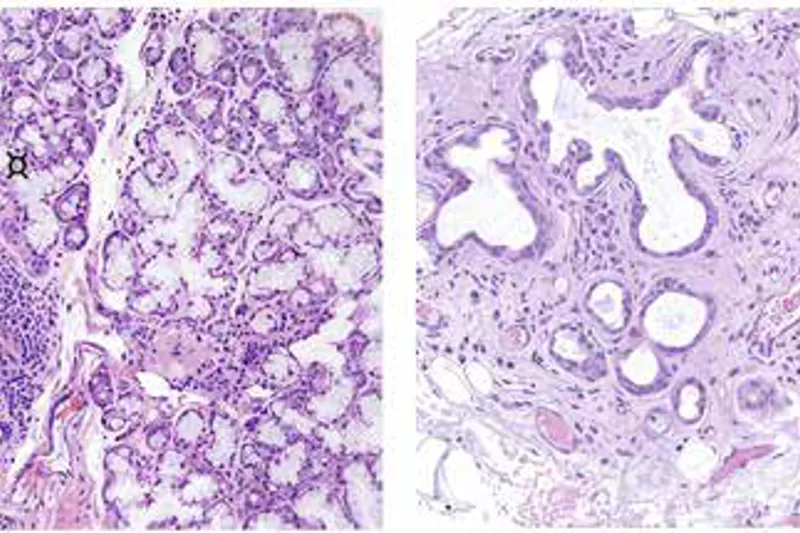

Hypofunktion af spytkirtlerne (objektivt påvist reduktion af spytsekretionen) og xerostomi (den subjektive fornemmelse af mundtørhed) er almindeligt forekommende tilstande. Patienter med nedsat spytsekretion og ændret sammensætning af spyttet har øget risiko for at udvikle caries, orale gær svampeinfektioner, mundslimhindeforandringer, invaliderende symptomer, synkebesvær og ændret smagsoplevelse. Den hyppigste årsag til xerostomi og nedsat spytsekretion er indtagelse af lægemidler, der påvirker den nervøse regulering af spytsekretionen. Strålebehandling af cancer i hoved og halsregionen medfører ofte permanent og alvorlig xerostomi og hypofunktion af spytkirtlerne som følge af degeneration af spytkirtelvæv, der ligger inden for strålefeltet. Sjögrens syndrom, en autoimmun sygdom der påvirker eksokrine kirtler, forårsager permanent xerostomi og hyposalivation på grund af immunmedierede forandringer i spytkirtlernes struktur. Aldring kan ligeledes medføre strukturændringer i spytkirtlerne, som kan påvirke spytsekretionen. Denne artikel giver en oversigt over ætiologi, patogenese, kliniske manifestationer, diagnostik og behandling af tilstande med nedsat spytkirtelfunktion, almindelige spytkirtelsygdomme (mucosacyster og spytsten) og spytkirteltumorer.

Salivary gland hypofunction (objective evidence of diminis hed salivary output) and xerostomia (the subjective sensation of dry mouth) are common conditions. Patients with salivary gland hypofunction and altered saliva composition are at increased risk for developing caries, oral fungal infections, oral mucosal changes and debilitating symptoms, swallowing problems, and diminished or altered taste. The most prominent cause of xerostomia and salivary gland hypofunction is the intake of medications interfering with the nervous regulation of salivary secretion. Radiotherapy for cancer in the head and neck region often leads to permanent and severe xerostomia and salivary gland hypofunction due to degeneration of the salivary gland tissue involved in the radiation field. Sjögren’s syndrome, an autoimmune disease affecting exocrine glands, causes permanent xerostomia and hyposalivation due to immunemediated structural changes in the salivary glands. Ageing may also be associated with structural changes in the salivary glands that can influence the functions of saliva. This article reviews the aetiopathogenesis, clinical manifestations, diagnosis, and management of conditions with salivary gland hypofunction, common salivary gland diseases (mucous cysts and sialoliths) and salivary gland tumours.